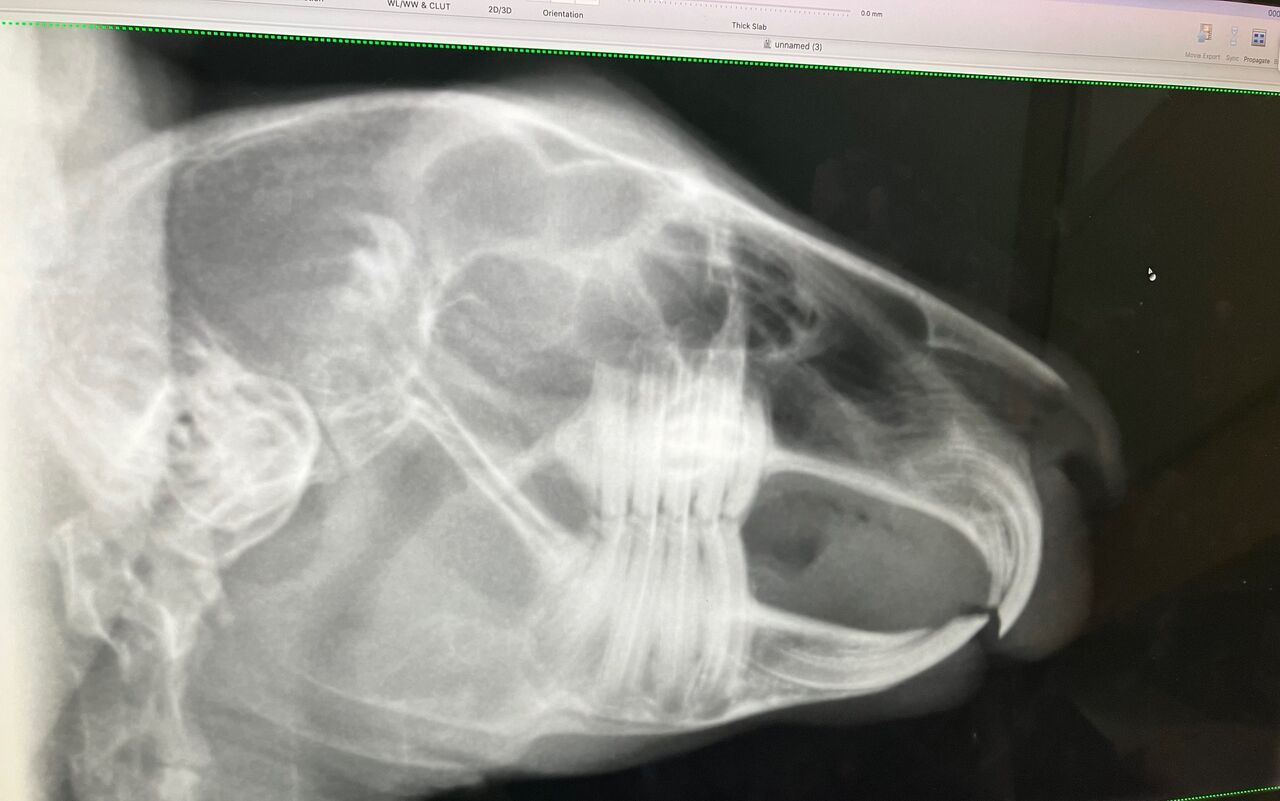

【血液検査とレントゲン】

※クリックで拡大見れます

奥歯(切歯)もキレイ、問題なし。

前歯(切歯)もご覧の通り問題なしっ!